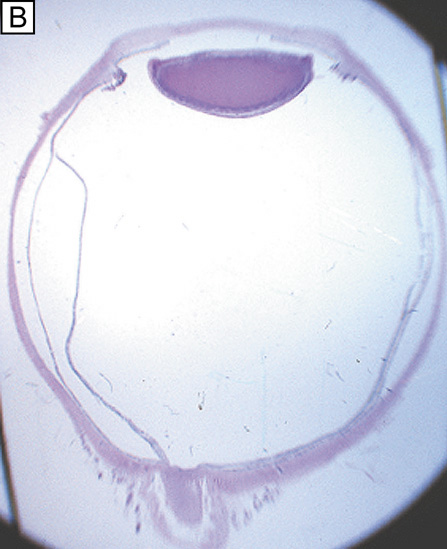

The endothelium of the infant cornea is composed of a single layer of approximately 500,000 neural crest-derived cells, each measuring around 5 μm in thickness by 20 μm in diameter and cover a surface area of 250 μm2.58,85 The cells lie on the posterior surface of the cornea and form an irregular polygonal mosaic. The tangential appearance of each corneal endothelial cell is uniquely irregular, usually uniform in size to one another, and typically six-sided (i.e., hexagons). They abut one another in an interdigitating fashion with 20 nm wide intercellular space between each other. The intercellular space is known to contain discontinuous apical tight junctions (macula occludens) and lateral gap junctions, thereby forming an incomplete barrier to diffusion of small molecules. As corneal endothelial cells have numerous cytoplasmic organelles, particularly mitochondrial organelles, they have been inferred to have the second highest aerobic metabolic rate of cells in the eye next to retinal photoreceptors.58

At birth, the central endothelial cell density of the cornea is around 5,000 cells/mm2.85 Because the corneal endothelium has very limited regenerative capabilities, there is a well-documented decline in central endothelial cell density with age that typical involves two phases: a rapid and a slow component.85,86 Due to corneal growth and age-related, or developmental, selective cell death, during the fast component, the central endothelial cell density decreases exponentially to about 3,500 cells/mm2 by age 5 years and 3,000 cells/mm2 by age 20 years.86 Thereafter, a slow component occurs where central endothelial cell density decreases to a linear steady rate of 0.6% per year, resulting in cell counts around 2,500 cell/mm2 in senescence (Fig. 20).85.86 Because endothelium maintains its continuity by migration and expansion of surviving cells, it is not surprising that the percentage of hexagonal cells decreases (pleomorphism) and the coefficient of variation of cell area increases (polymegathism) with age.86

It is important when reviewing this information to realize that these are average central corneal endothelial cell measurements from predominantly Caucasian U.S. populations, as racial and geographic differences can exist. Also, understand that this data applies only to central corneal endothelial measurements because recent work has shown that higher cell densities can typically be found in more peripheral aspects of the cornea (Fig. 21).87 Therefore, based on these studies, it appears that central corneal endothelial cell numbers decrease on average about 50% from birth to death in normal subjects. Because corneal decompensation typically does not occur until central values reach around 500 cells/mm2, there appears to be plenty of cellular reserve potential remaining after an average human life span.86 Estimates suggest that healthy, normal human corneal endothelium could maintain corneal clarity up to a minimum of 215 years of life, if humans lived that long.85

Having a sufficient number of endothelial cells to cover the posterior surface of the cornea along with having integrity of their cell junctions (tight and gap junctions), which are present in the intercellular spaces between endothelial cells, establishes the barrier function of endothelium (Figs. 12 and 22, 23, and 24). Clinically, the barrier function of the cornea can be assessed in vivo by the use of specular microscopy or confocal microscopy (endothelial cell density) or fluorophotometry (permability). In healthy human eyes, this barrier prevents the bulk flow of fluid from the aqueous humor to the corneal stroma, but does allow moderate diffusion of nutrients, water, and other metabolites to cross into the stroma through the 20 nm wide intercellular space. This leaky endothelial barrier may initially seem inefficient, but when one considers that most nutrients for all layers of the cornea come from the aqueous humor, the situation is reasonable.